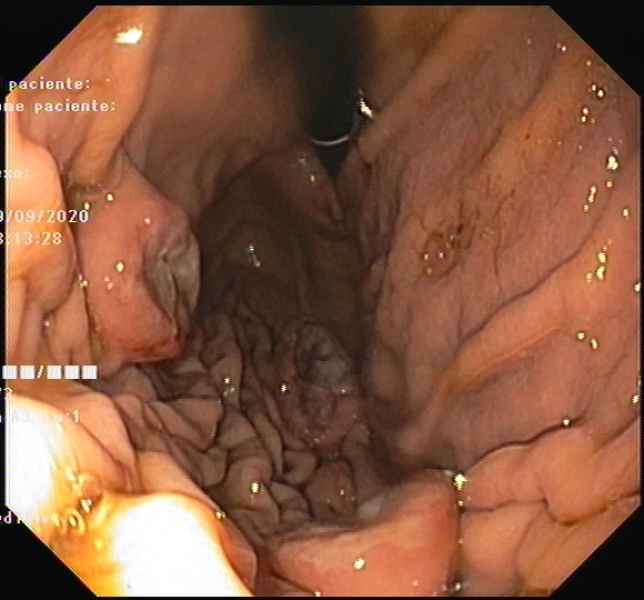

Gastric Crohn's disease